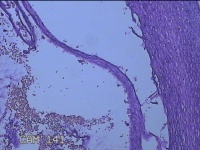

宫颈3点、9点、11点、12点组织

性别

女

年龄

37岁

临床诊断

人乳头瘤病毒感染

一般病史

HPV其他12型阳性

标本名称

大体所见

1.“宫颈3点组织”:灰白粉红色组织1x0.8x0.2cm一块。 2.“宫颈9点组织”:灰白粉红色组织0.7x0.5x0.2cm一块。 3.“宫颈11点组织”:灰白粉红色组织0.8x0.5x0.2cm一块。 4.“宫颈12点组织”:灰白粉红色组织8.5x0.5x0.2cm一块。

图1